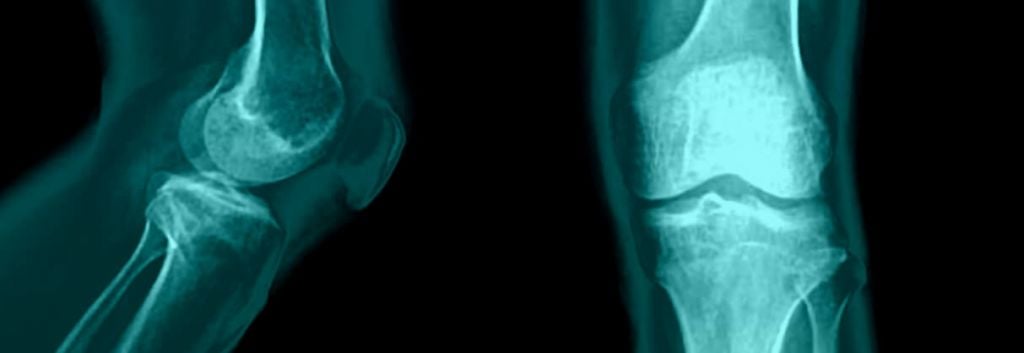

German Biotech’s Gene Therapy for Osteoarthritis Plucked by US Pharma By Alex Dale 3 minutesmins December 14, 2017 -Updated: onJune 23, 2022 3 minutesmins Share WhatsApp Twitter Linkedin Email Newsletter Signup - Under Article / In Page"*" indicates required fieldsInstagramThis field is for validation purposes and should be left unchanged.Subscribe to our newsletter to get the latest biotech news!By clicking this I agree to receive Labiotech's newsletter and understand that my personal data will be processed according to the Privacy Policy.*Company name*Job title*Business email* GeneQuine’s gene therapy for osteoarthritis in the knee has been acquired by US pharma company Flexion Therapeutics for up to $64M.GeneQuine is developing a gene therapy for the treatment of osteoarthritis. It uses helper-dependent adenoviruses, which provide long-term expression, a higher packaging capacity, reduced immunogenicity and they do not integrate into the host genome. It seems like yesterday that GeneQuine pitched in our Startup Battle at Refresh, but today, the company has announced that its osteoarthritis candidate has been acquired by Flexion Therapeutics. The deal could be worth up to $64M (€54M) if development progresses well and approval is achieved.Osteoarthritis is a condition that commonly affects joints in the knee, hips fingers and toes, with approximately 27 million people living with the condition in the US alone. The end of a bone is covered by cartilage, but this breaks down in osteoarthritis, making it painful and difficult to move a joint. As the disease progresses, small nicks of bone or cartilage can come away and float around in the joint. An inflammatory response produces cytokines and enzymes, which cause further damage.GeneQuine has developed a potentially disease-modifying drug for the condition in both humans and animals. The candidate, FX201, is a locally administered gene therapy – which should help to prevent its removal by the lymphatic system – that helps the body to express interleukin (IL)-1 receptor antagonist, an anti-inflammatory protein, in infamed joints. A sustained reduction of inflammation by the therapy reduces pain, which make a massive impact on the patient’s daily life.During preclinical studies, a single injection of the therapy could induce the expression of IL-1Ra in a joint for a least a year. Kilian Guse, CEO of GeneQuine, highlighted the benefits of the project being taken over by Flexion: “Given their [Flexion] deep expertise in osteoarthritis drug development, they will be able to advance the program into the clinic and potentially to the market.” Initially, FX201 will be targeted at patients with aggressive osteoarthritis of the knee.Current treatments are unable to counter the disease, so biotech is on the lookout for treatments that can modify the disease. Ablynx is preparing to enter the clinic with one of its nanobodies, which has seen it receive its first milestone payment from a deal with Merck, while Medivir will begin the clinical development of its drug, MIV-711, which breaks down collagen that may contribute to osteoarthritis progression. Controlling pain remains important though, and Levicept hopes to do this without the dangerous side effects that are associated with nonsteroidal anti-inflammatory drugs.Suggested Articles Enhanc3D Genomics raises £10M to advance technology platform Gilead boosts oncology pipeline with XinThera acquisition Argenx’s Rare Disease Treatment Strikes Gold in Phase III Gate Neurosciences emerges from stealth to tackle CNS diseases Cell reprogramming can reverse fibrosis after heart attack It is exciting to see so many different approaches being taken to try and find a solution to osteoarthritis. GeneQuine’s technology is particularly exciting as it could offer a long-term, maybe even one-time, correction to the disease.Images – Tewan Banditrukkanka / shutterstock.com; Tefi / shutterstock.comImmunology & inflammation R&D trends and breakthrough innovations Inpart’s new report provides scientific decision-makers with a roadmap of high-impact I&I opportunities, emerging technologies, and potential future partners. Download now Explore other topics: GermanyInflammatory disease ADVERTISEMENT